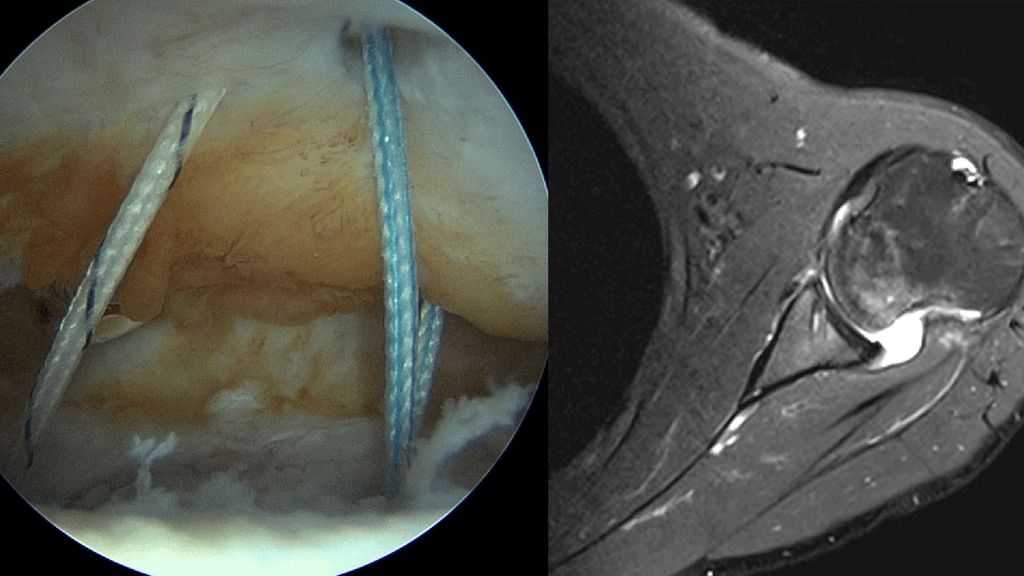

Zusätzlich zur Kapsel-Labrum-Refixation wird in zunehmendem Maße eine Remplissage (unanatomische Kapsulotenodese der Infraspinatussehne) empfohlen, dies insbesondere bei Revisionseingriffen, bei sehr sportlichen Patienten, besonders Kontaktsportlern und Patienten mit hohem funktionellem Anspruch und einer hohen Rezidivgefahr57,58 (Abb. 4a, 4b). Ursprünglich für Patienten mit großen Hill-Sachs-Defekten empfohlen („off-track“ Läsionen), ist in jüngerer Zeit eine deutlich großzügigere Indikationsstellung zur Remplissage auch bei „on-track“ Läsionen festzustellen.59 Für arthroskopische Bankartoperationen mit zusätzlicher Remplissage sind deutlich geringere Versagerraten und bessere Sportfähigkeit beschrieben.60 Die früher beklagte signifikante Einschränkung der Beweglichkeit nach einer Remplissage konnte in der neueren Literatur nicht bestätigt werden.61

Abb. 4a, b: Zusätzlich zur Kapsel-Labrum-Refixation wird in zunehmendem Maße eine Remplissage empfohlen, dies insbesondere bei Revisionseingriffen, bei sehr sportlichen Patienten mit hohem funktionellem Anspruch und einer hohen Rezidivgefahr